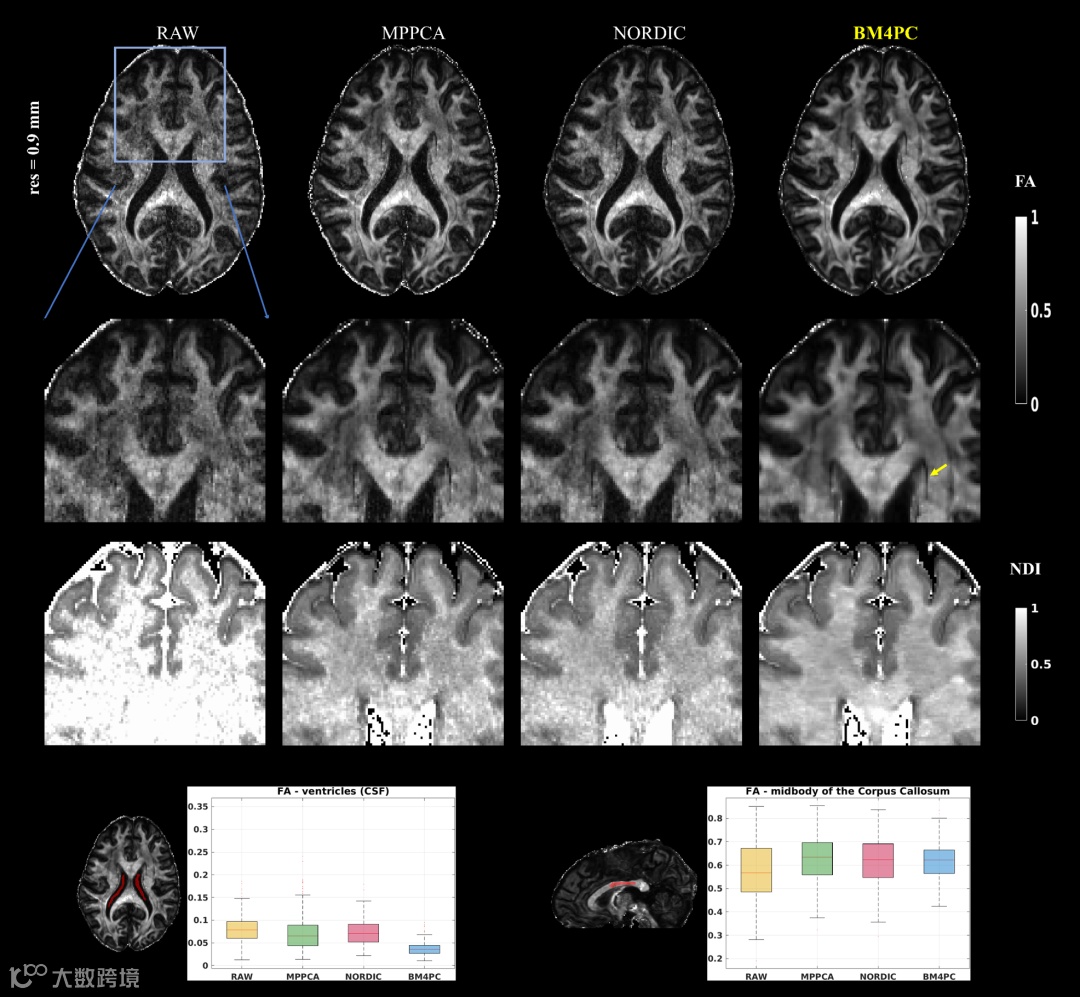

FA and neurite density index (NDI) maps of Dataset 1c – (0.9mm res.).

Note the detail preservation provided by BM4PC, highlighted by the yellow arrow.

The boxplot graphs show FA values calculated in two ROIs. BM4PC achieves the lowest mean and standard deviation (std) for the CSF region.

All methods achieve similar mean values for the CC region, with BM4PC having the smallest std.

(CSF – left; midbody of CC – right)